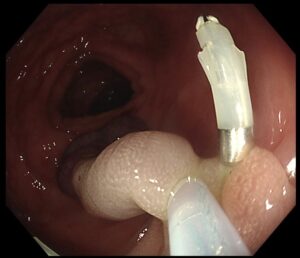

✔ まずクリップでポリープの茎をしっかり把持し、血流を遮断(写真2,3)

(写真3)